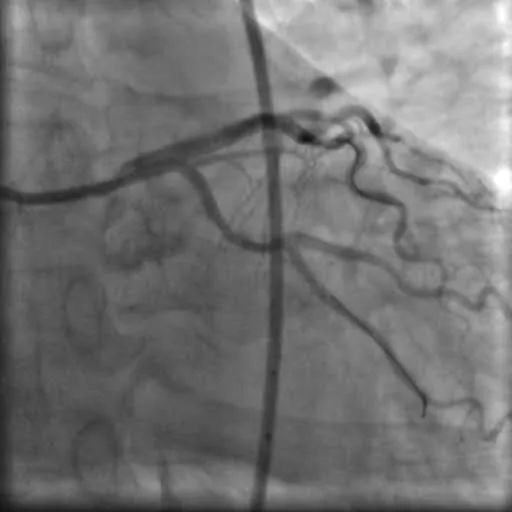

入院后,杨大爷很快在心血管介入中心进行了冠状动脉造影及血管内超声检查术,结果显示:左主干末端至前降支近段,回旋支开口都有严重狭窄且伴钙化。如果再推迟入院几天,很有可能发生猝死。

造影及血管内超声显示两枚支架均贴壁良好,前降支及回旋支开口管腔狭窄显著改善,前向血流良好。

造影图